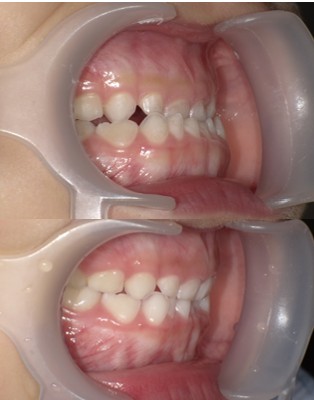

小児の上顎前突(出っ歯)

成長期に用いられる機能的な可撤式矯正装置

・診断:上顎前突

・年齢:7歳5ヵ月

・使用した主な装置:機能的な矯正歯科装置(取り外し可能)

・抜歯部位:なし

・治療期間:12ヵ月

・通院回数:12回

・費用の目安:矯正料金として40万+税金。診断料金6万5千円+税金。調整処置料金:月3500円税込を12回で4万2千円。総額 553.500円